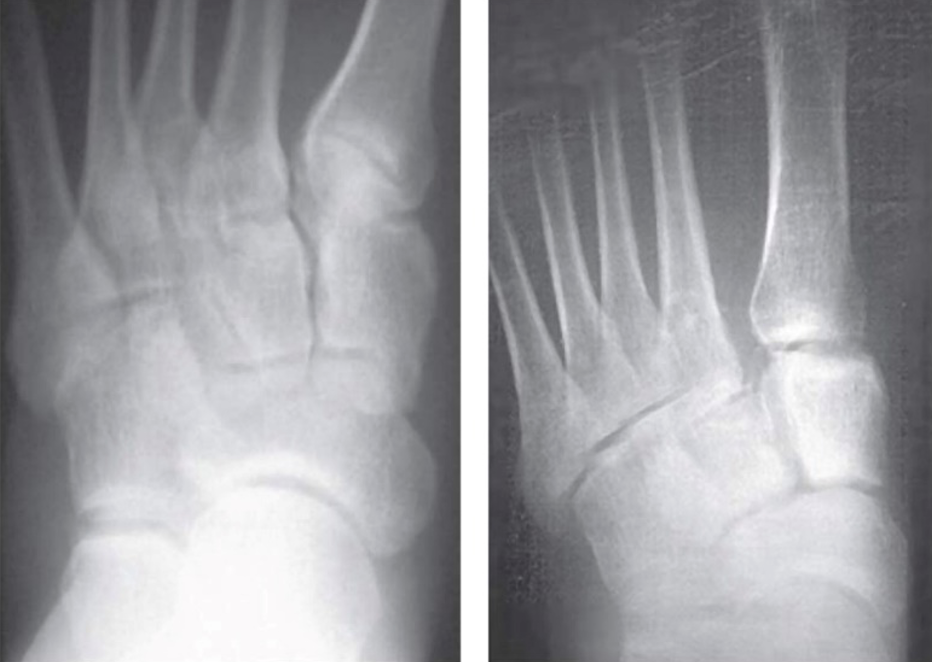

The "fleck-sign" (Fig. 10), an avulsion fracture of the base of the second metatarsal or medial cuneiform, is pathognomonic of a Lisfranc injury. (21) The radiograph shows a disruption of the C2-M2 alignment (red dotted line), a widening of M1-M2 (double-headed arrow), and a small fragment of bone ("fleck" sign) between M1-C2 (white arrow.) There is also a fracture of the cuboid (black arrow).